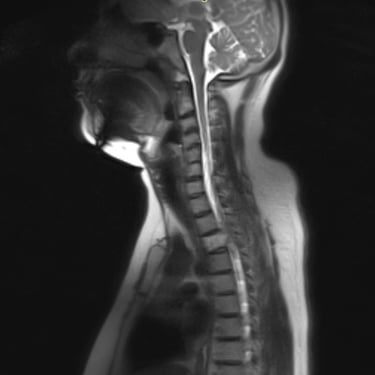

Tumor vertebral dorsal hemorrágico: descompresión medular, biopsia y artrodesis dorsal

El tumor vertebral dorsal puede ocasionar compresión de la médula espinal, dolor intenso y alteraciones neurológicas progresivas. En algunos casos, estos tumores presentan componente hemorrágico que incrementa la presión sobre las estructuras nerviosas. El tratamiento quirúrgico puede incluir descompresión medular para liberar la médula espinal, toma de biopsia para establecer el diagnóstico histopatológico y artrodesis dorsal con instrumentación para estabilizar la columna vertebral. Este abordaje permite reducir el riesgo de daño neurológico, aliviar los síntomas y mantener la estabilidad vertebral. La cirugía se realiza con técnicas especializadas que buscan preservar la función neurológica y mejorar la calidad de vida del paciente.